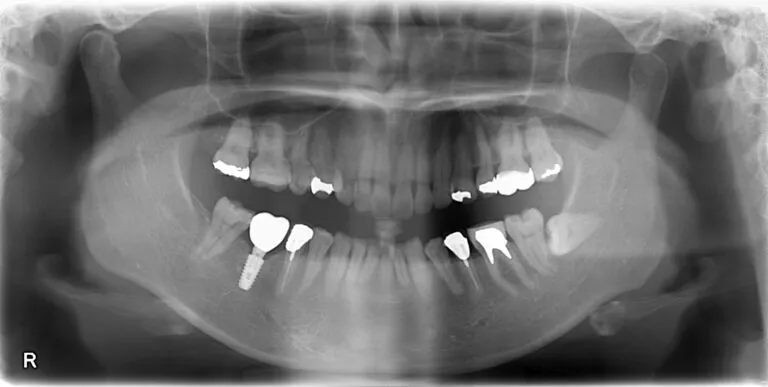

実際の当院での症例としてレントゲンを見ていきましょう。

49歳女性。

2011年に当院にインプラント埋入。

レントゲン画像の左下を注目ください。奥から二番目の歯にインプラントが入っているのがわかります。また画像左下の一番奥の歯に関しては特に大きく削る処置をしていないのが分かります。

インプラントではなく、ブリッジでもしっかり噛むことは可能な症例でしたが、仮にブリッジをここで作った場合はこの一番奥の歯は大きく削られ、歯にかかる負担も大きくなり、もしかしたら2011年から現在までの間にそのブリッジがダメになっていた場合もありえるでしょう。